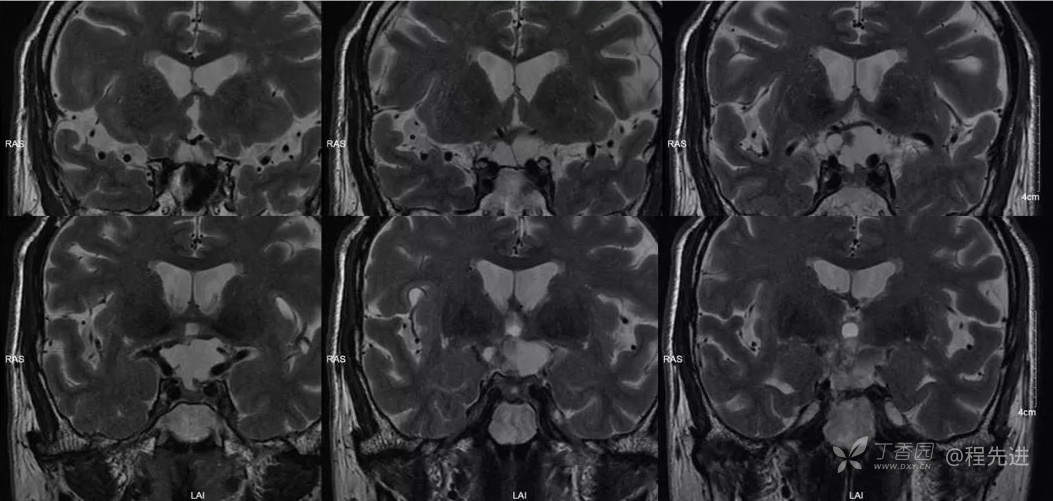

img

T2冠状位